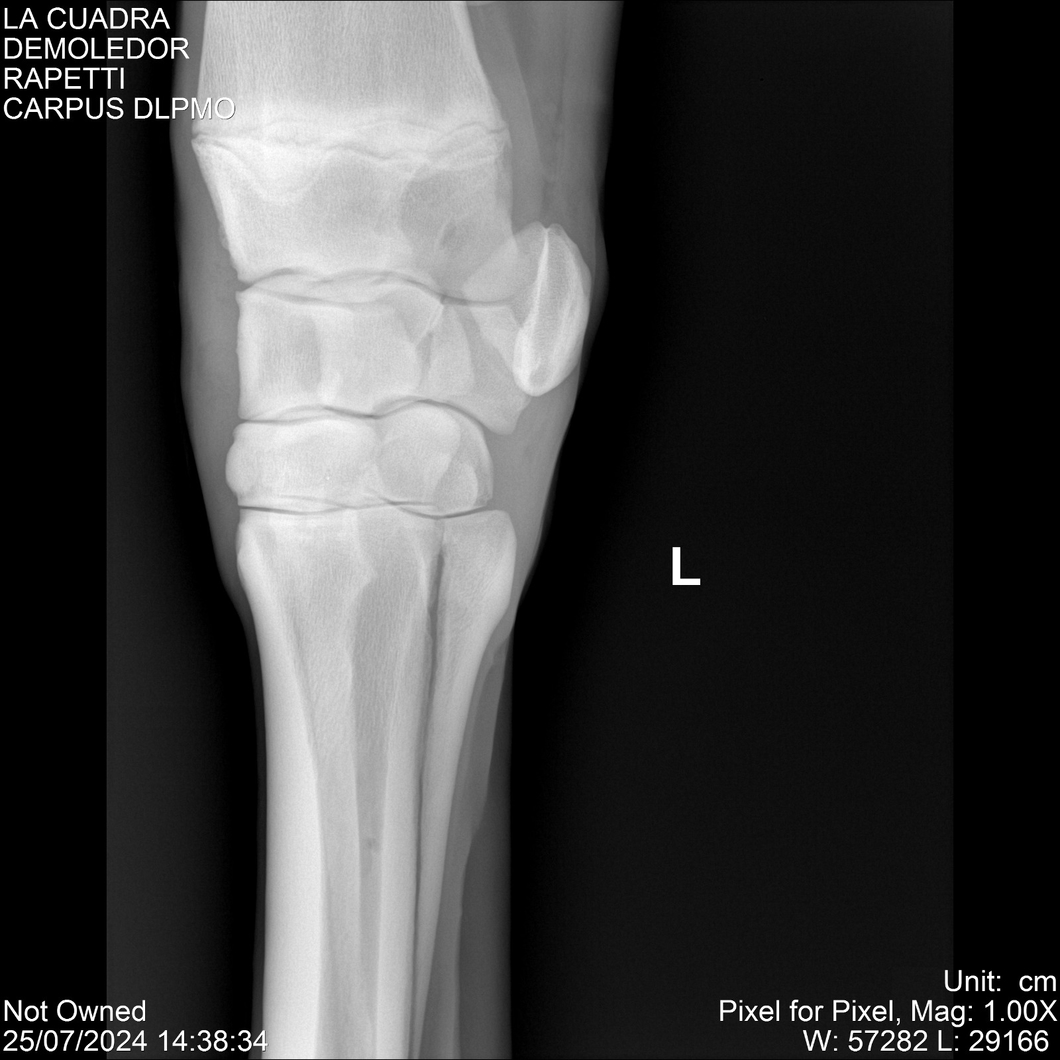

LOTE 14, DEMOLEDOR 🔥 🔥 🔥 Lote Anterior Volver al remate Lote Siguiente Ficha Contacto Montevideo - Ficha del Lote Identificador: #284454 Categoría: Yeguarizos Montevideo - 89 Visualizaciones ClicData Contacto Empresa: Abelenda N. R., Walter Hugo Nombre*: Teléfono* : E-mail* : Mensaje Enviar Registrese gratis Este contenido Exclusivo está disponible sólo para usuarios registrados Ingresar